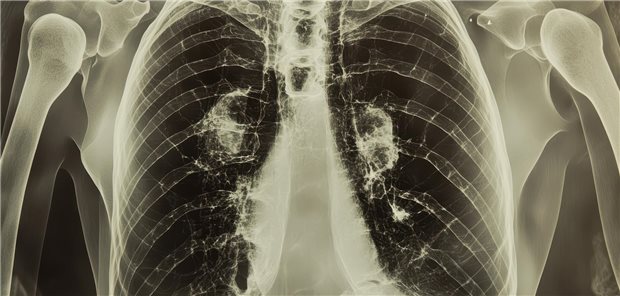

US-Studie: Kleine Lungenrundherde bei Männern mit Seminomen sind zwar häufig, meist aber harmlos

23.10.2024